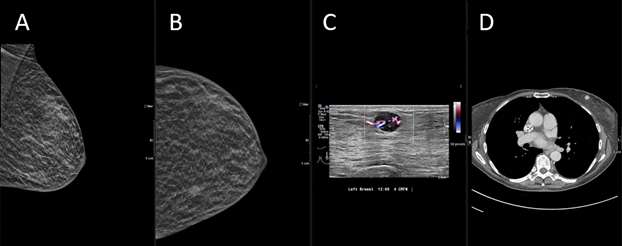

Breast metastasis from possible appendiceal carcinoid tumor:

Case 4: